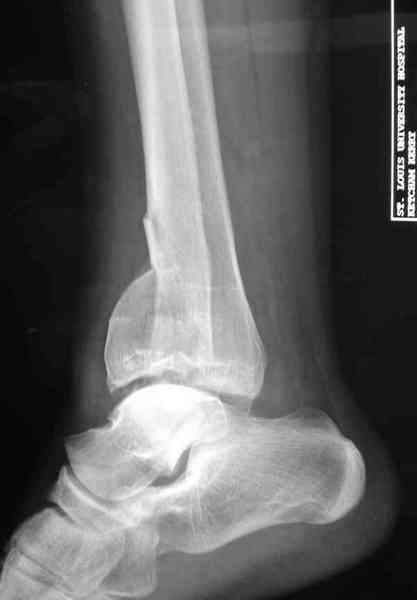

Дополнительные ренгенограммы после дистракции и

обязательная комьютерная томография дают возможности разузнать топографию расположения фрагментов, что немаловажно для планирования хирургического доступа.

По апексу фрагмента ориентируется при планировании

фиксации, также предоперационно определяется

направление фиксирующего материала: шурупа или спицы с упорной площадкой.

Здесь выставлена пара случаев перелома пилона, оба

случая леченные этапным наружным фиксатором.